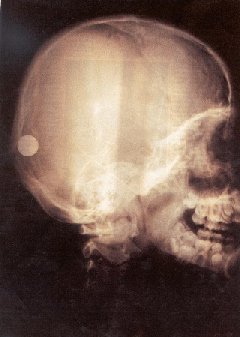

They easily pass through soft body

tissues, but they are somewhat blocked by hard material

like bones.

X-ray of a person's head

X-rays are almost completely stopped by